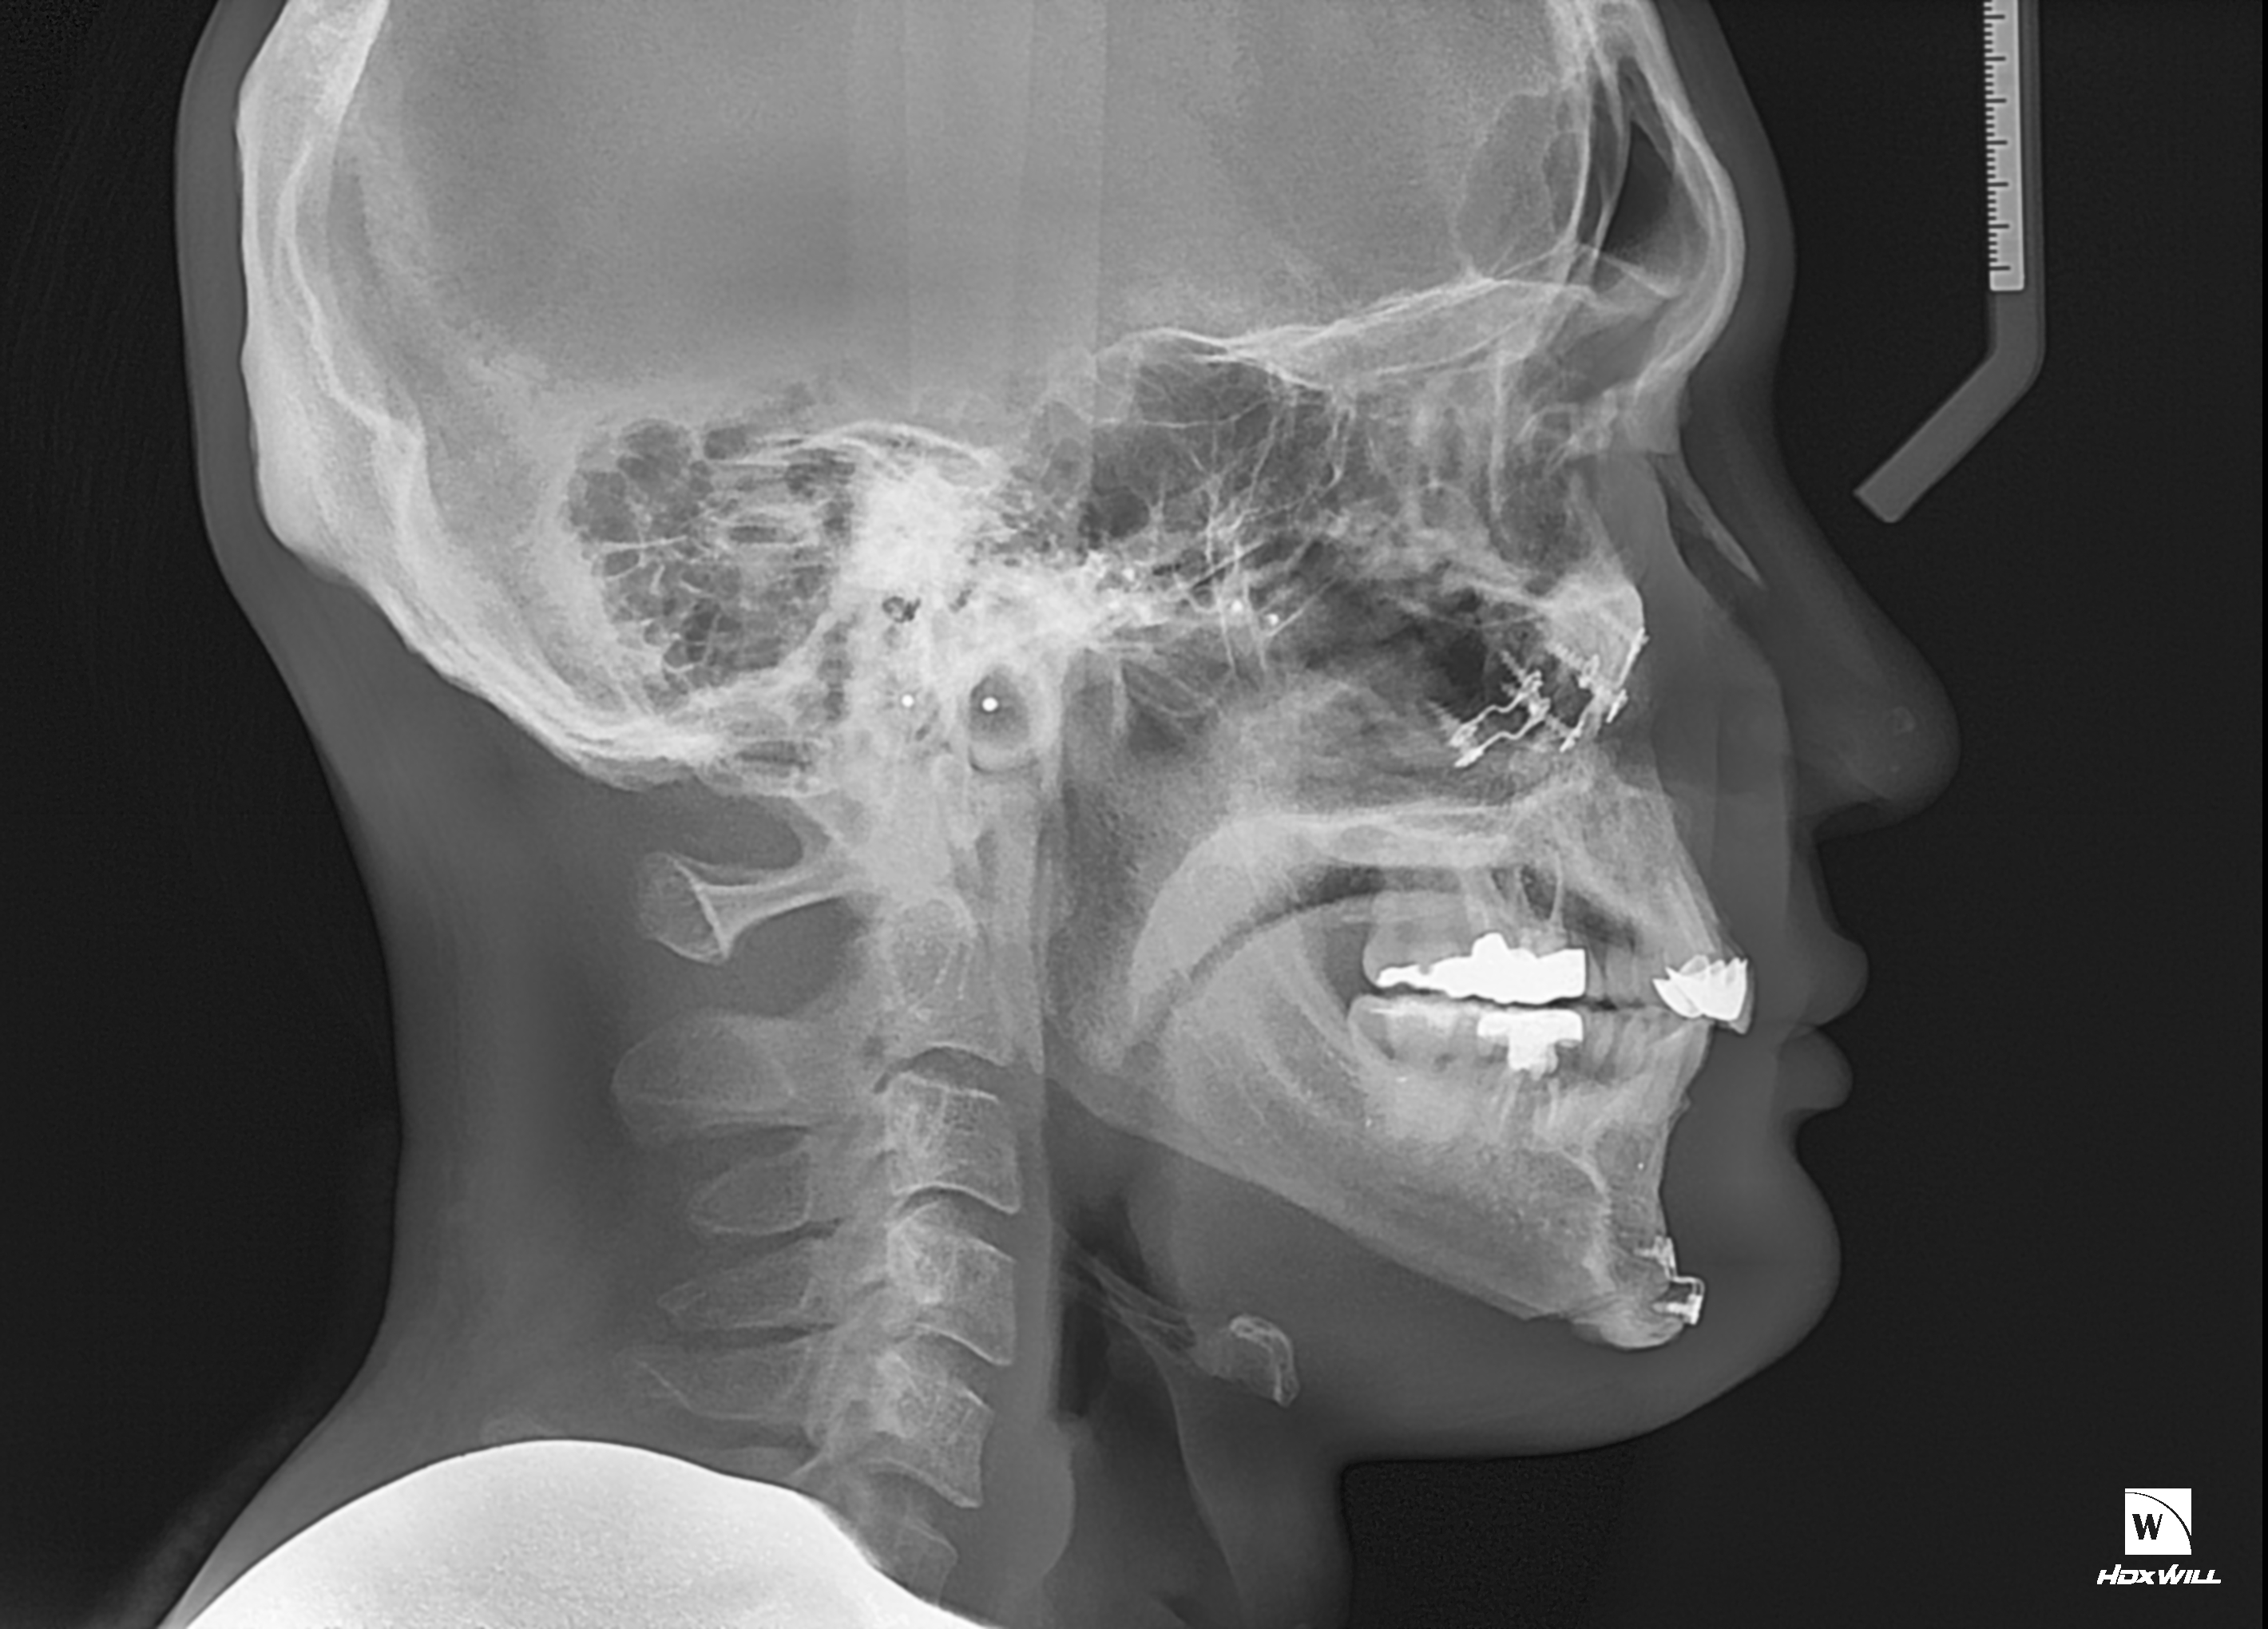

1. 현재 제가 수술 전후 ct를 올리겠습니다

2. 일차 양악 수술후 경미한 주걱턱 때문에 쉐이빙을 했는데 효과는 미미했습니다 진짜 쉐이빙은 효과가 미흡

3. 그 후 어드벤스를 3mm정도 했습니다

4. 현재 주걱턱 처럼 보여서 돌아버리겠습니다..

5. 음 어느 선생님 말을 빌리면 턱끝 절골라인이 너무 아래서 절골되어서 그런거다 신경선으로 부터 5~10mm정도 아래서 절골후 약간 사선으로 2mm 정도만 전진시키면 두꺼운 근육이 얇아지면서 좀 편해진다 이게 맞는말인가요???

6. 아니면 지금 상태에서 다시 절골한곳 다시 절골해서 뒤로 후퇴시켜야되나요?

7. 지금 현재 턱끝 포지션은 좋은가요?

8. 아래 제가 도완 한 대로 수술하면 어떨까요? 길이도 줄이면서 후퇴도 시키고